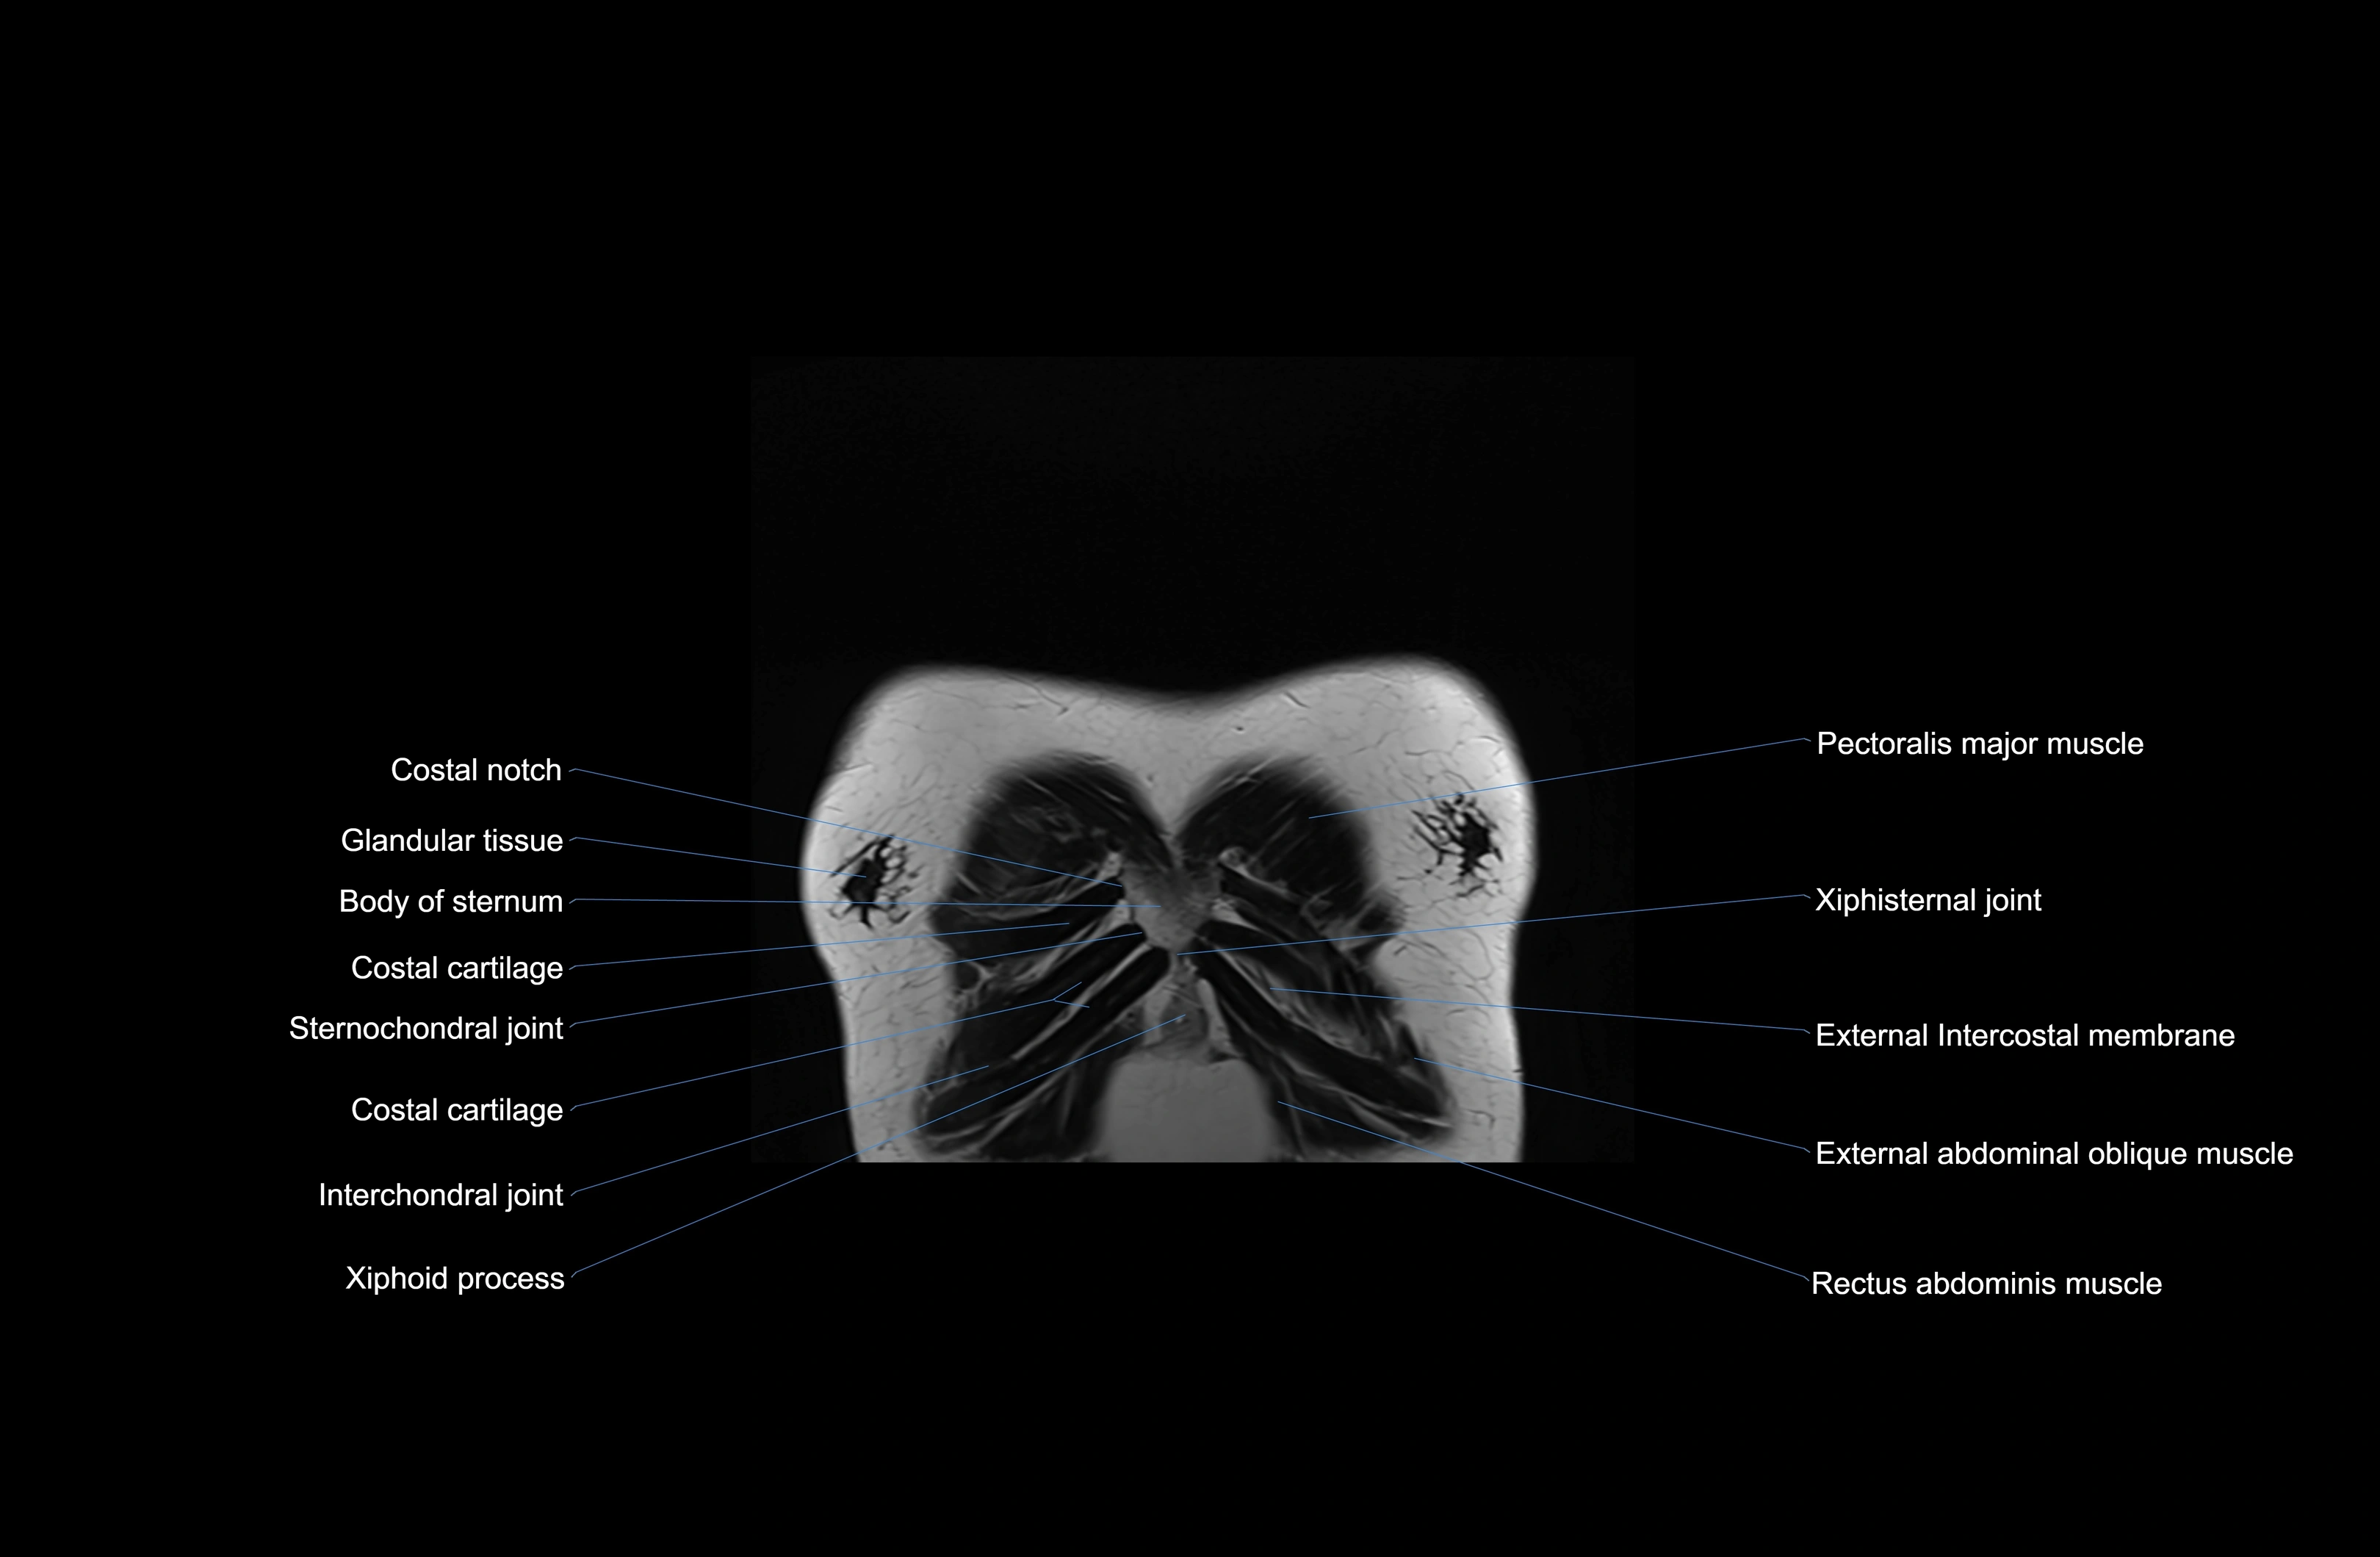

MRI images